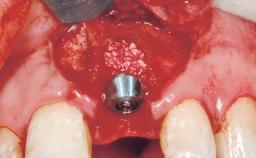

Late Flapless Placement of an Implant in a Maxillary Left Central Incisor Site

A 39-year-old male patient presented with a chief complaint of discomfort and gingival discoloration around his maxillary left central incisor. He was in good general health and was a non-smoker. His past dental history was significant because of the traumatic fracture of tooth 21 in a sporting accident at age 13. Initial dental treatment included endodontic therapy and a full-coverage restoration. The patient became symptomatic 5 years later, when structural failure of the tooth resulted in the dislodgment of the crown. Endodontic retreatment, apical surgery, and post-and-core restoration were performed.

Bone Volume Deficient horizontally, requiring prior grafting